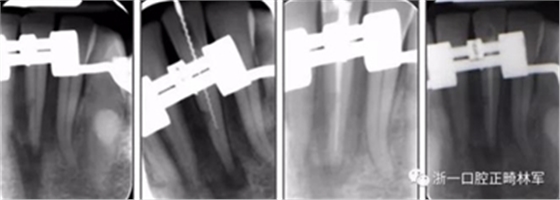

術(shù)后第9天開(kāi)始旋轉(zhuǎn)擴(kuò)弓器,每天轉(zhuǎn)2次,每次轉(zhuǎn)90度,即擴(kuò)開(kāi)0.5mm。每隔1周進(jìn)行檢查,目標(biāo)上頜擴(kuò)開(kāi)9mm,下頜擴(kuò)開(kāi)6mm。18天后,上頜中切牙間出現(xiàn)8mm間隙。下頜出現(xiàn)6mm間隙,(于13天出現(xiàn)后,停止旋轉(zhuǎn)擴(kuò)弓器)。在擴(kuò)弓器旋轉(zhuǎn)3天后,拍片發(fā)現(xiàn)左下頜中切牙遠(yuǎn)中牙根中段有一條低密度陰影,臨床冷熱診反應(yīng)遲鈍,可能為術(shù)中損傷所致。牙體牙髓科會(huì)診,建議行根管治療,故行根管治療。

擴(kuò)弓保持8周后,除擴(kuò)弓器影響牙外粘接托槽,使用0.014鎳鈦絲進(jìn)行排齊、整平。旋轉(zhuǎn)停止后3個(gè)月拆除擴(kuò)弓器,全口粘接托槽,使用0.016niti繼續(xù)排齊整平。佩戴可摘保持器,保持上頜寬度。在使用至0.018x0.018niti7周,徹底排齊整平后,使用大弓型的0.016x0.022不銹鋼絲,繼續(xù)維持原有寬度,同時(shí)停止使用可摘保持器。掛II類(lèi)牽,糾正磨牙關(guān)系,使用鏈圈關(guān)閉散在間隙,少量使用IPR去除局部前牙的黑三角。術(shù)后9個(gè)月拍全景示,牙根平行度可,再無(wú)其他牙根出現(xiàn)問(wèn)題。1年7個(gè)月后治療結(jié)束。上下頜3-3舌側(cè)保持器+哈雷氏保持器進(jìn)行保持。